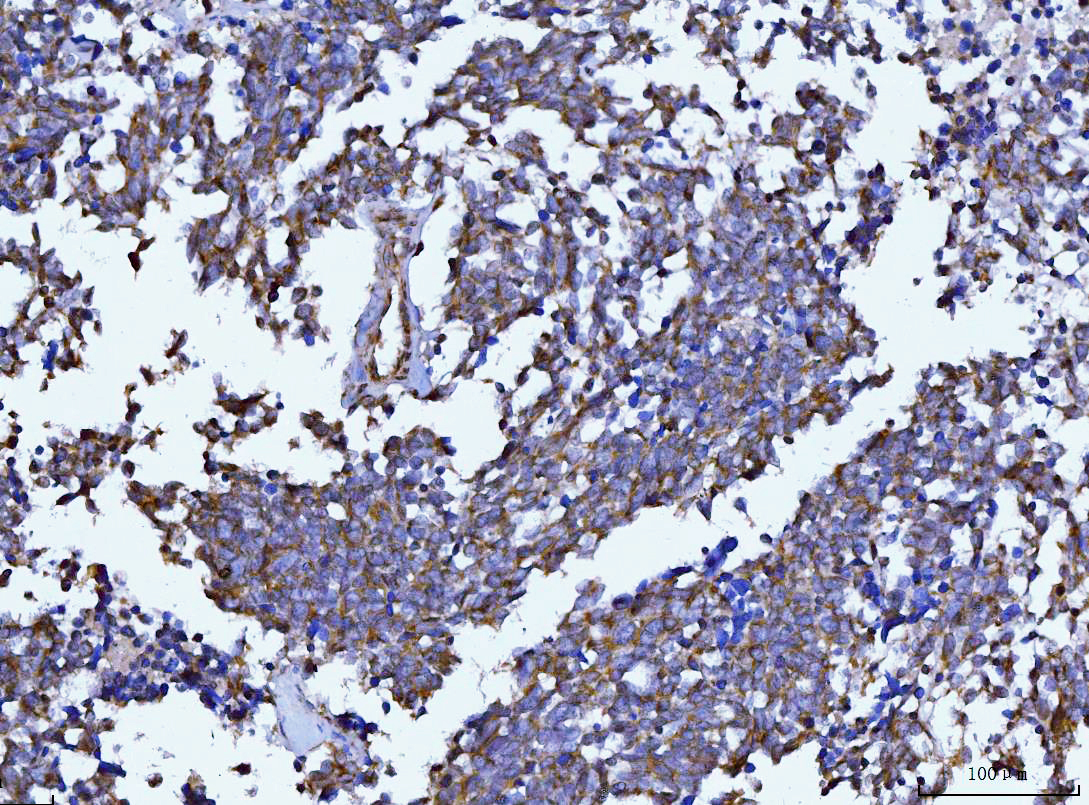

IHC analysis of Beclin 1/BECN1 using anti-Beclin 1/BECN1 antibody (M00327-2).

Beclin 1/BECN1 was detected in a paraffin-embedded section of human lung cancer tissue. The tissue section was incubated with mouse anti-Beclin 1/BECN1 Antibody (M00327-2) at a dilution of 1:200 and developed using HRP Conjugated mouse IgG Super Vision Assay Kit (Catalog # SV0001) with DAB (Catalog # AR1027) as the chromogen.